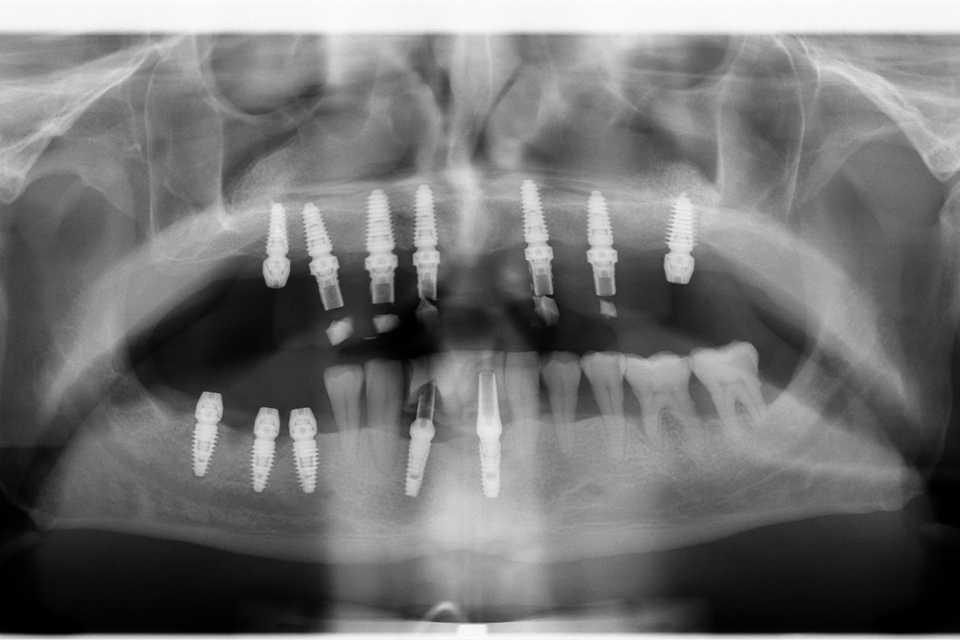

În urma consultului de specialitate, s-a decis extracția dinților parodontotici și a unei lucrări vechi, urmată de inserarea a 7 implanturi dentare Mega-Gen AnyRidge, cu adiții osoase și sinus lift bilateral. Implanturile au fost poziționate strategic pentru a permite o reabilitare protetică completă, formată din 14 dinți, asigurând astfel zâmbetul dorit de pacient.

Lucrarea protetică este fixă, înșurubabilă pe suport multiunit, realizată din ceramică pe suport de titan.